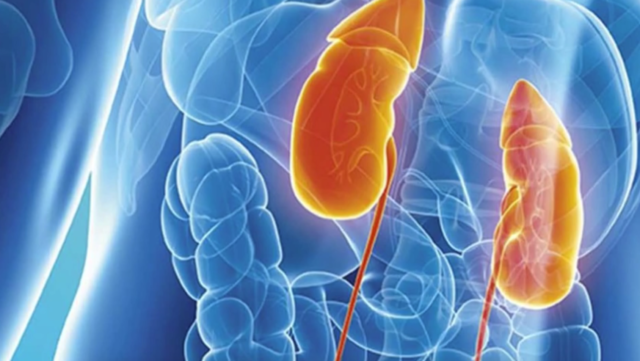

El Instituto Mexicano del Seguro Social (IMSS) en Chihuahua, a través de la Coordinación de Salud Pública, emitió una serie de recomendaciones para el adecuado cuidado de los riñones.

La coordinadora de Salud Pública, doctora Brenda Ramírez Vega, explicó que la principal función de los riñones es la de eliminar las toxinas del organismo contenidas en la sangre.

Indicó que las enfermedades renales se suelen denominar “asesinos silenciosos”, porque durante años no dan manifestaciones, pero cuando se manifiestan influyen considerablemente deteriorando la calidad de vida de la persona. Asimismo, la coordinadora señaló que quienes tienen altos niveles de colesterol son más propensas a sufrir un problema renal, por lo que es recomendable la reducción del consumo de grasas.

“El riñón es un órgano compuesto por venas y arterias que se endurecen con altos niveles de colesterol, perdiendo paulatinamente su capacidad de filtración”, recalcó.

Ramírez Vega destacó que los alimentos que más hacen trabajar a los riñones, en el proceso de su eliminación, son las proteínas que se encuentran, sobre todo, en la carne, el pescado y los huevos, que al consumirlos con moderación son importantes en una dieta balanceada.

La médica advirtió que la falta del consumo de agua natural favorece la aparición de enfermedades renales, formación de cálculos en el riñón e infecciones urinarias. Finalmente, exhortó a los derechohabientes del IMSS acudir anualmente a los módulos de PrevenIMSS, ubicados en las Unidades de Medicina Familiar, para recibir orientación y atención oportuna de salud.